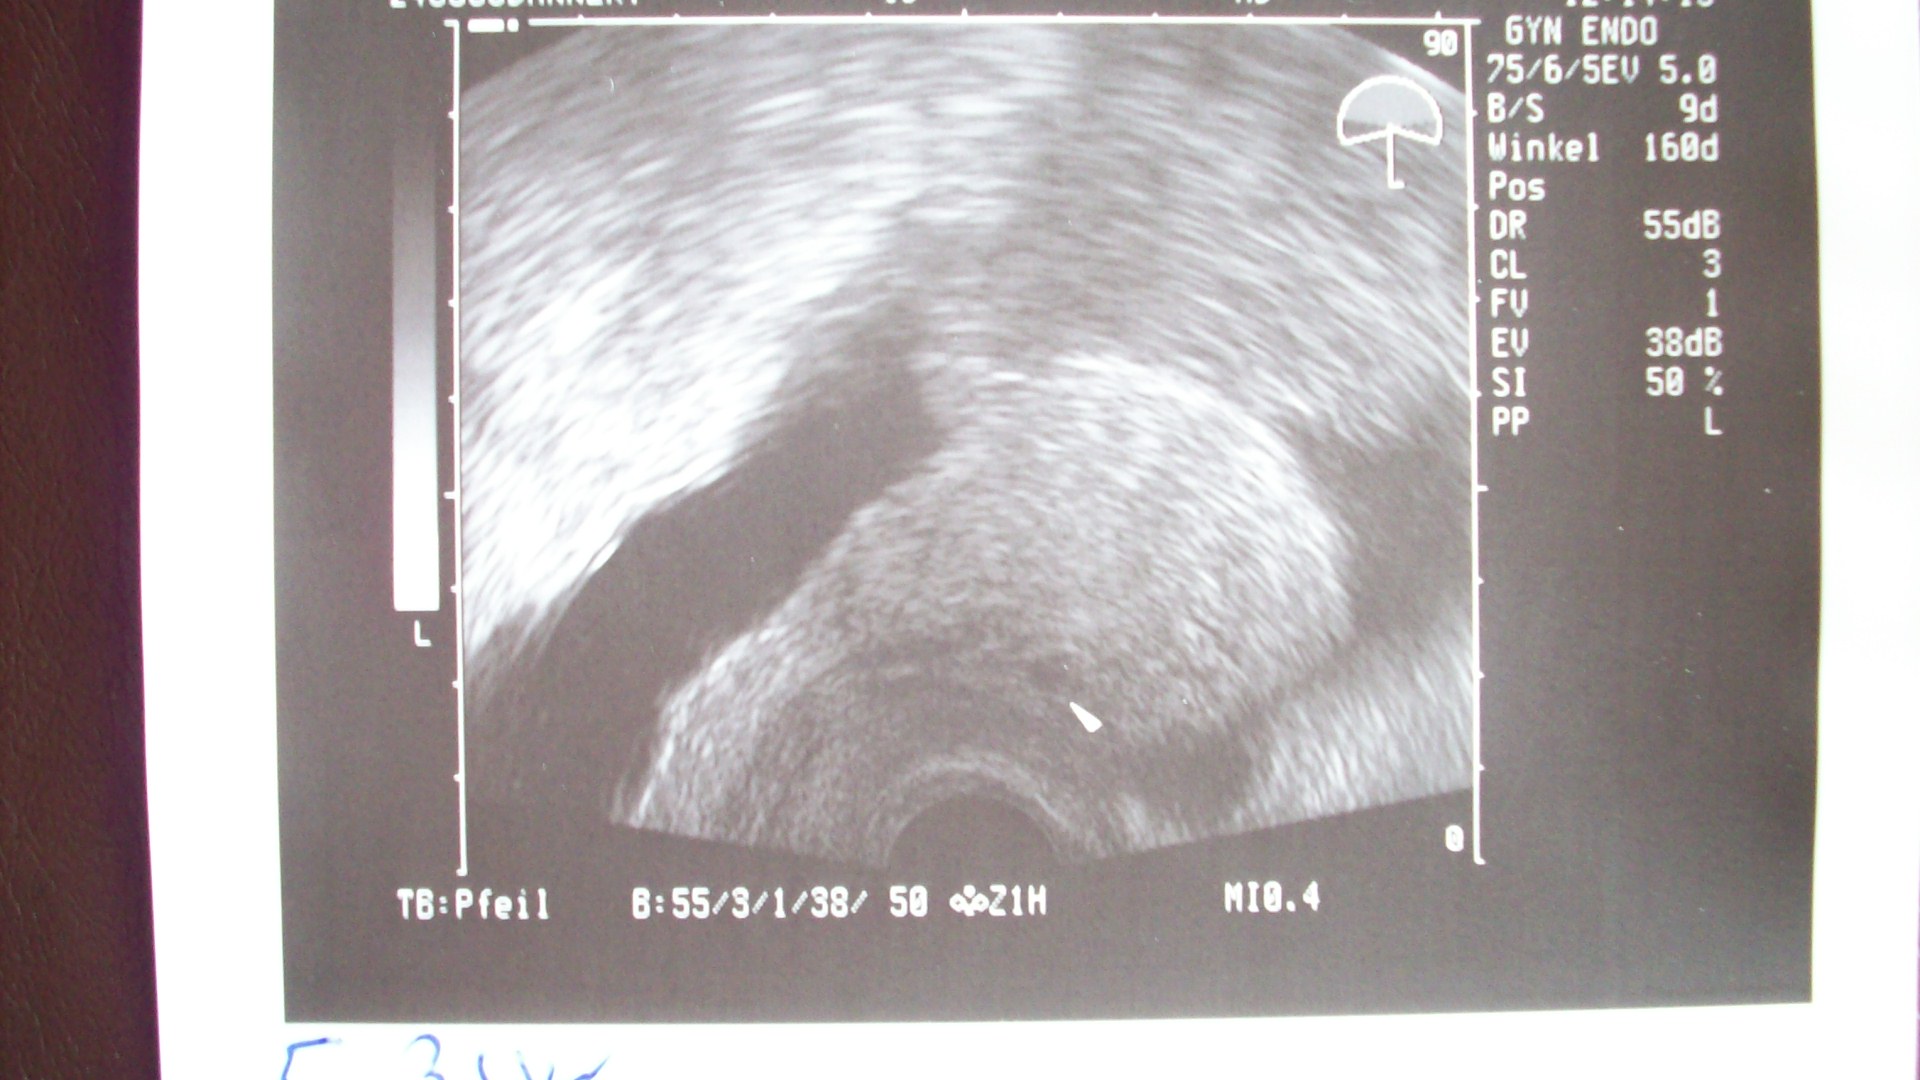

bikerbabe, wenn du unter "Antwort schreiben" gehst, dann gibt es unten "Attachement hinzufügen". Dort kannst du unter "Dateiname" und durchsuchen ein Bild von deiner Festplatte auswählen und es in deinen Beitrag hochladen. Eine Größenbeschränkung kenne ich da nicht. Versuchs mal, ansonsten schick mir mal eine PN.